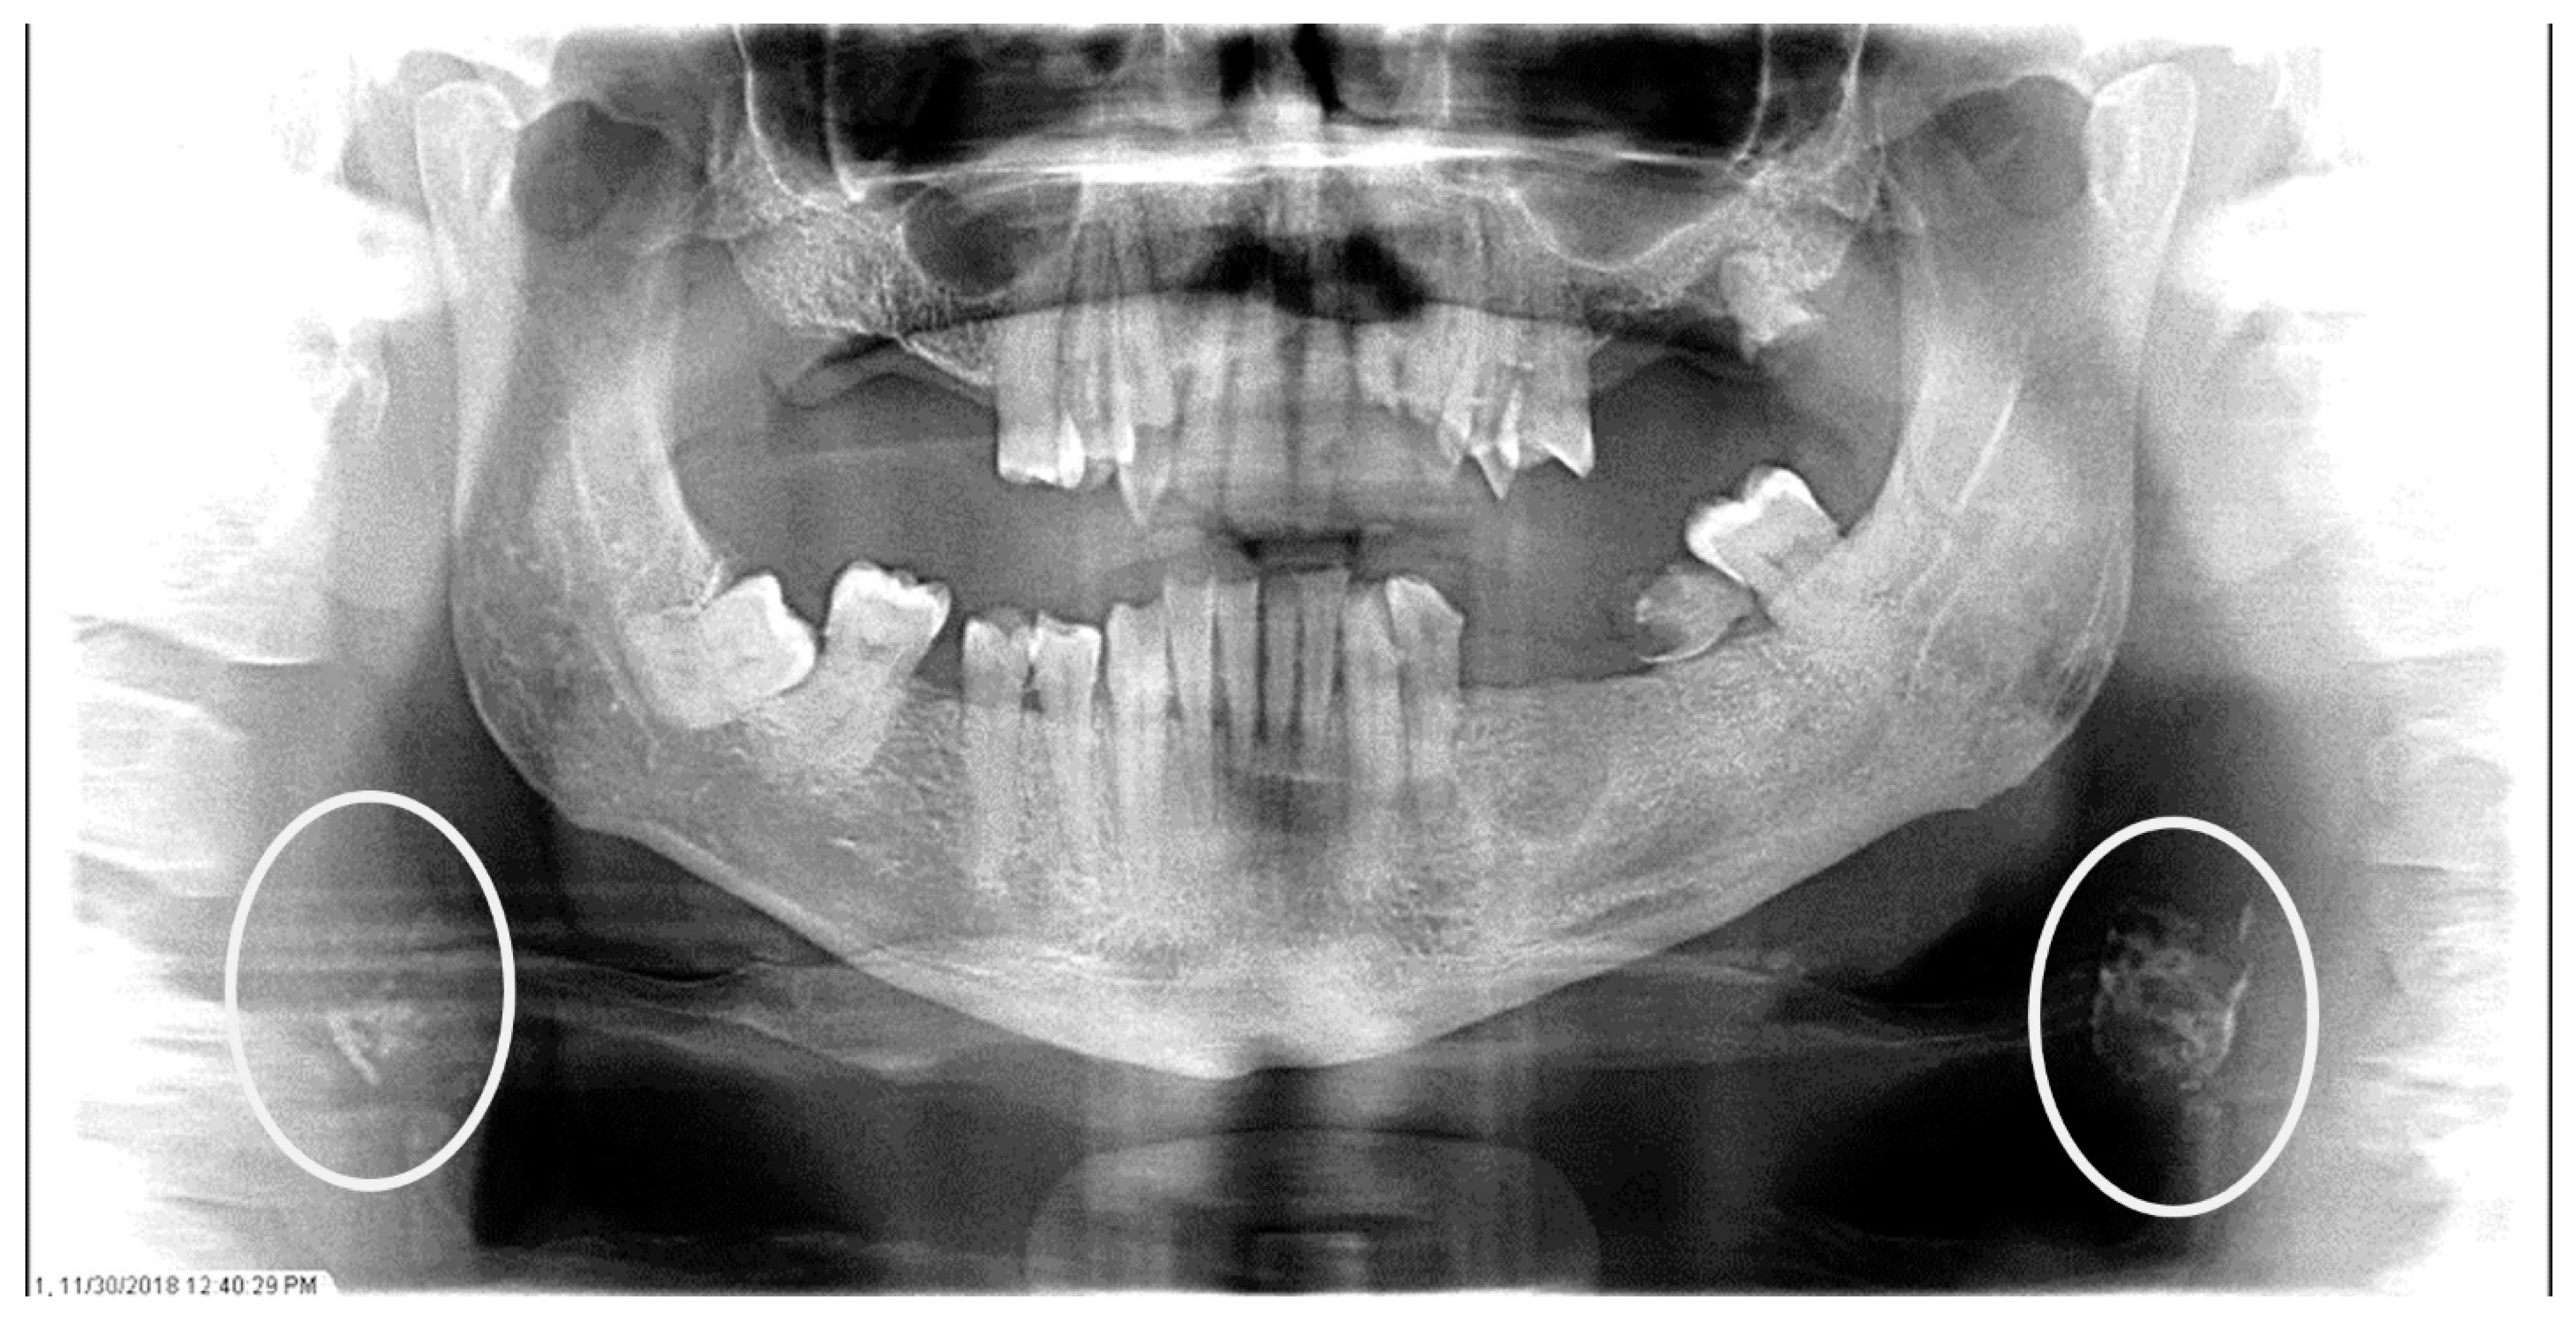

Figure 2.

The panoramic radiograph of a 77-year-old female patient with a medical history of hypertension, hyperlipidemia, diabetes mellitus, and coronary artery disease showing a unilateral left carotid artery calcification (CAC) during a comprehensive dental examination. The CAC is encircled by a white line.